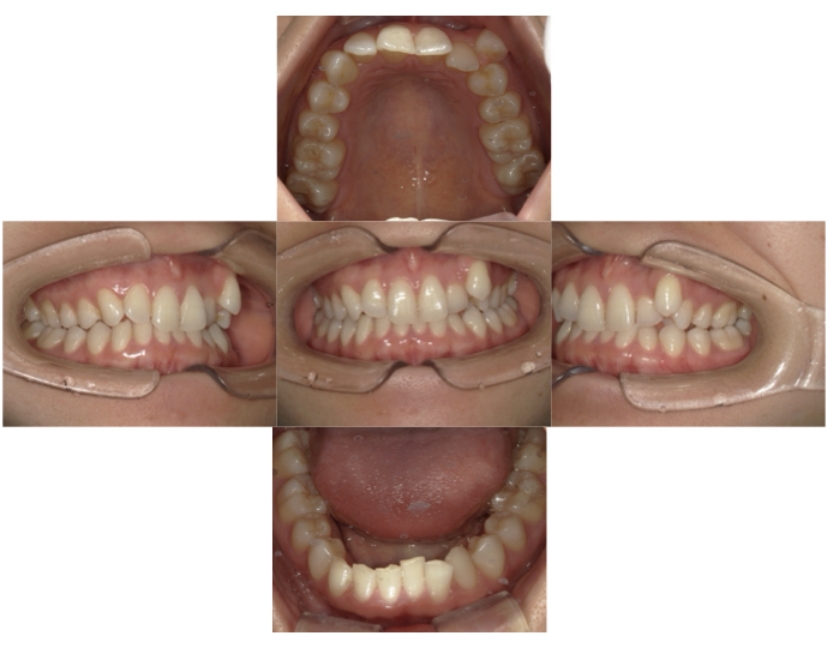

BEFORE

AFTER

上顎前突、叢生

抜歯

ブラケット矯正

上下顎叢生、上顎前突(出っ歯、上下の前歯のガタガタ)のケースです。

装置はラビアル(上下表側)で、上顎の小臼歯を2本抜歯を行っています。抜歯したスペースを使って、上の前歯の後方移動と叢生(ガタガタ)と出っ歯の改善を行っています。下は歯と歯の間にIPR(隣接面削合)を行い、スペースを確保し、叢生の改善を行っています。

主訴 前歯のガタガタと出っ歯が気になる。

年齢・性別 47歳 女性

お住まいの地域 神奈川県川崎市

治療方針 抜歯スペースおよびIPRを利用して上前歯の叢生(ガタガタ)の改善

抜歯部位 上顎左右第一小臼歯

使用装置 ラビアル(上下表側)、顎間ゴム

治療期間 2年0か月

治療回数 15回

リテーナー クリアリテーナー